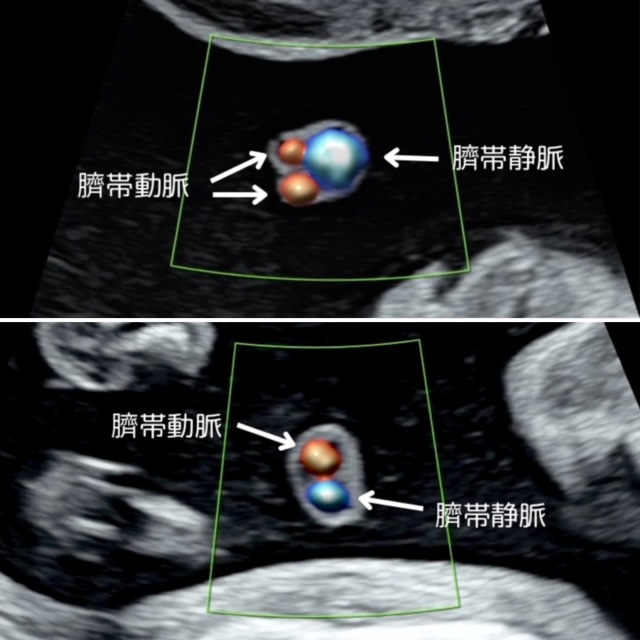

【正常な臍帯と単一臍帯動脈】

上段の写真は正常な臍帯断面です。臍帯は動脈2本、静脈は1本、合計3本の血管が束なっていますので、断面はミッキーマウスのように〇が3つ見られます。下段の写真では、臍帯動脈は1本しかありません。これを「単一臍帯動脈」といいます。正常であれば3本の血管が見えるのですが、動脈が1本なので合計2本しか見えません。